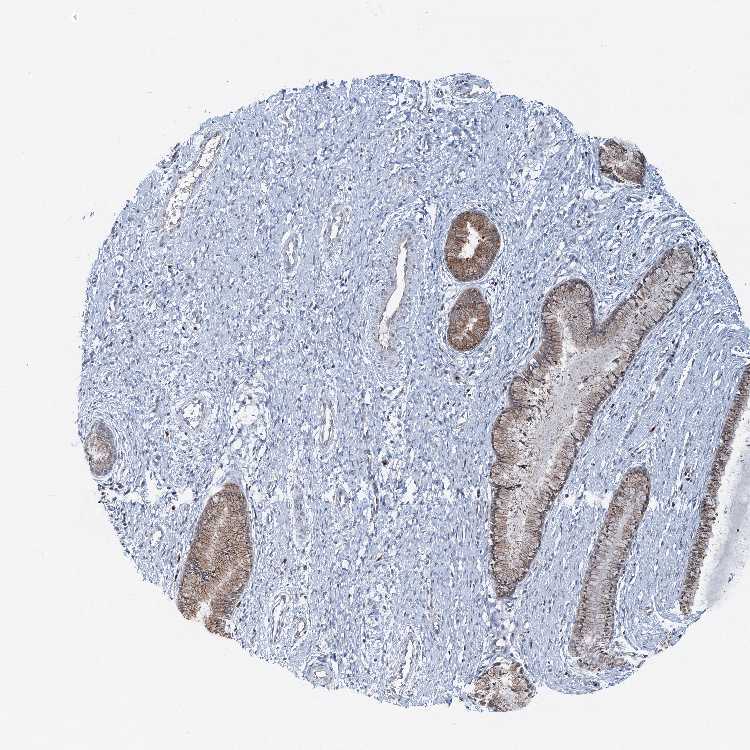

CERVIX - Antibody stainingi

Antibody staining in the annotated cell types in the current human tissue is reported as not detected, low, medium, or high, based on conventional immunohistochemistry profiling in selected tissues. This score is based on the combination of the staining intensity and fraction of stained cells.

Each image is clickable and will lead to virtual microscopy that enables deeper exploration of all samples and also displays staining intensity scores, fraction scores and subcellular localization as well as patient and tissue information for each sample.

Antibody HPA040749

Glandular cells Medium

Squamous epithelial cells Not detected